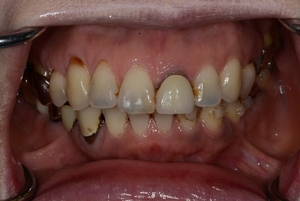

〇ご相談内容:歯並びがよくない〇矯正の種類:マウスピース型矯正「インビザライン」〇治療期間:39週間〇治療費用:44万円(税込)